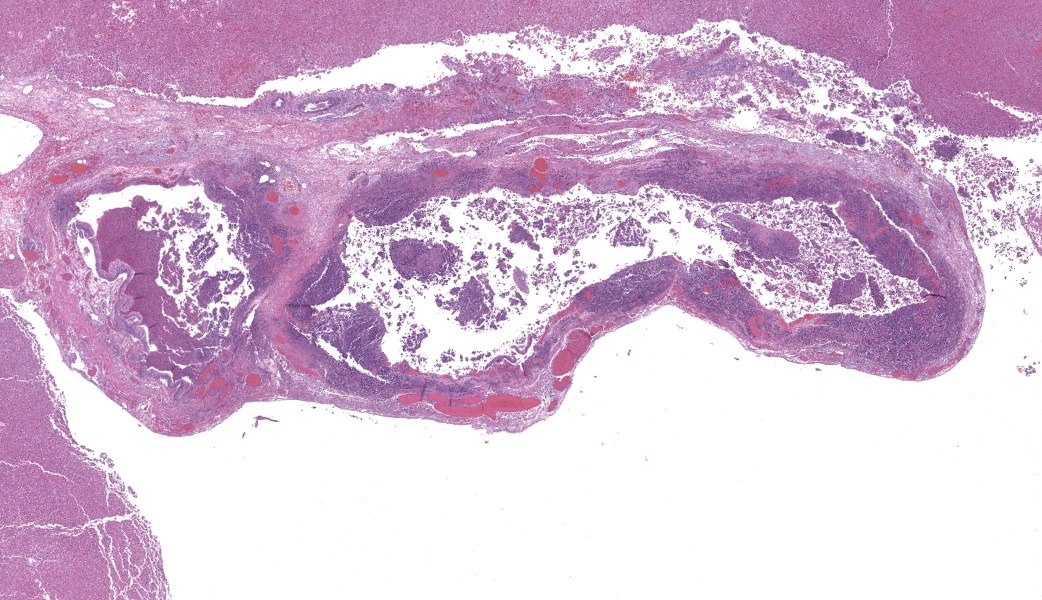

Microscopic Description:

Gallbladder and liver: The gallbladder and adjacent portal tracts are effaced by multifocal to coalescing areas of coagulative and lytic necrosis admixed with foci of suppurative inflammation. The gallbladder is transmurally severely expanded by numerous neutrophils, scattered lymphocytes and histiocytes, abundant polymerized fibrin, necrotic debris eosinophilic proteinaceous fluid (edema), extravasated red blood cells (hemorrhage), and mats of extracellular rod-shaped bacteria (bacilli). Multifocally, blood vessels in the gallbladder are distorted by endothelial and/or mural necrosis and innumerable bacilli. Some vessels are partially occluded by fibrin and bacterial thrombi. Remaining intact vessels are congested. There is marked loss of gallbladder epithelium characterized by hypereosinophilia and loss of nuclear detail (necrosis), occasionally seen sloughing into the lumen admixed with neutrophils, fibrin, and red blood cells. Throughout the liver, bile ducts and portal vasculature undergo similar changes of varying severity (Fig 2). Bacilli are located extracellularly within portal areas and within sinusoids or intracellularly within macrophages. There are moderate, acute, multifocal loss of hepatocellular detail admixed with areas of fragmented chromatin and karyolytic debris (coagulative and lytic necrosis). Remaining hepatocytes are mildly to moderately swollen by small to medium-sized, round, clear, cytoplasmic vacuoles.